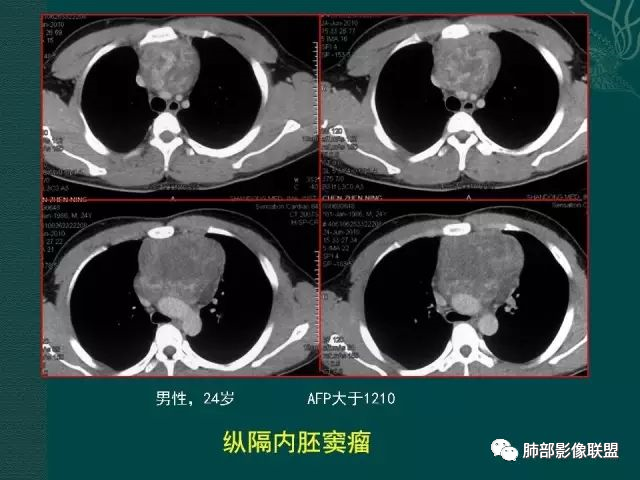

精原细胞瘤

临床缺乏特异性,几乎见于男性,一般血清LDH升高,部分β-HCG轻度升高,精原细胞瘤不产生AFP,血AFP升高可考虑非精原细胞瘤或混合生殖细胞肿瘤。影像表现一般肿块巨大,分叶状,边界不清,可浸润性生长,无钙化及脂肪,有纤维分隔,轻中度强化,易转移。

男性,32岁,精原细胞瘤

内胚窦瘤(卵黄囊瘤)

是高度恶性生殖细胞肿瘤,卵黄囊细胞是唯一产生AFP的细胞,所以AFP升高是卵黄囊瘤或含有卵黄囊成份的生殖细胞肿瘤最重要的特征,其中卵黄囊瘤一般大于1000ug/L;影像表现肿块体积往往较大,易坏死囊变,易侵犯周围结构及转移。